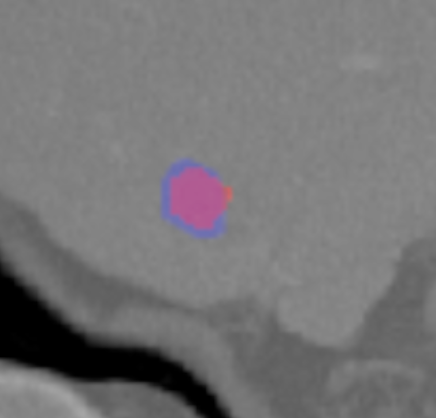

Each pixel of the image is assigned to one of the two classes liver/other tissue and tumor/other tissue, respectively, with a certain probability. Results of the automated liver and tumor segmentation are visualized in Figure 3.2. Comparison with ground truth and segmented liver and tumor give rise to the assumption that our approach is highly promising for obtaining high performance metrics. To qualitatively evaluate performance, we applied some of the commonly used evaluation metrics in semantic image segmentation. Performance metrics are summarized in Table 1.